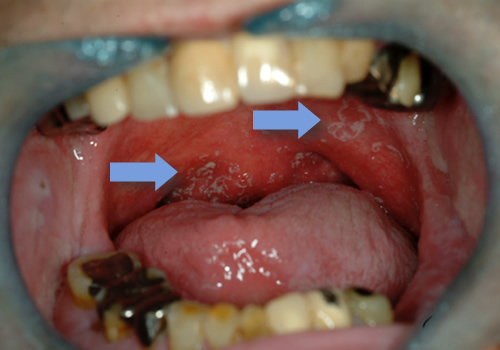

口腔扁平苔癬

口腔扁平苔癬は、罹患率が0.5〜3%で女性に多いと言われています。白色の網目状、レース状を呈する、ガーゼなどでぬぐい取れない病変で、赤色部分が混在する場合もあります。典型的なものは肉眼所見でも診断できる場合があります。

びらんや潰瘍を伴う場合は、疼痛も自覚します。WHO(世界保健機関)では、前がん状態とし取り扱われており、約2〜3%程度悪性化するとの報告もあります。